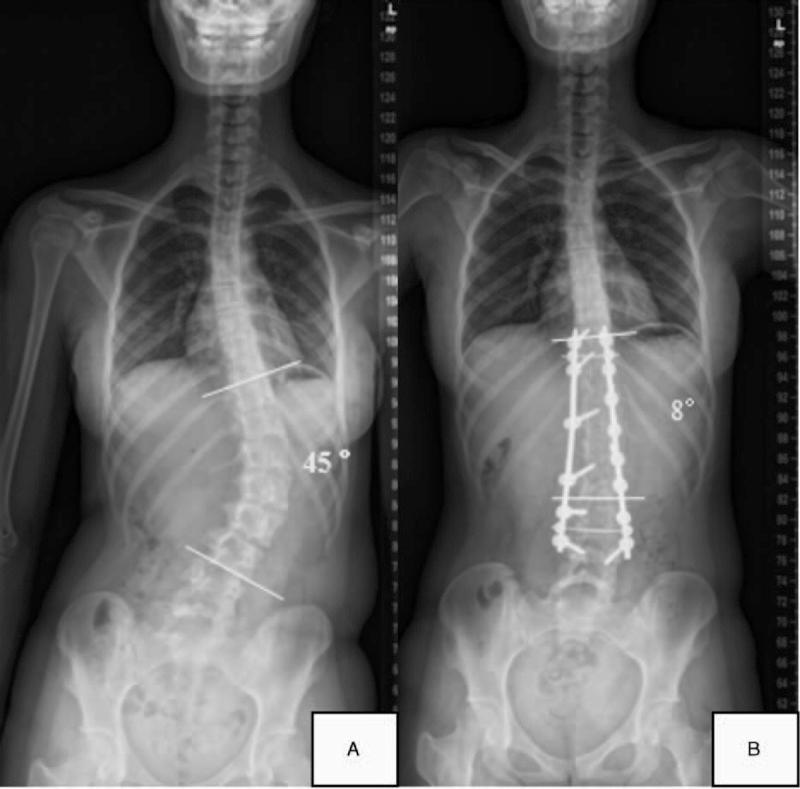

The primary aim was to compare postoperative radiographic outcomes between sexes among adolescent idiopathic scoliosis (AIS) patients. A total of 162 AIS patients (42 males and 120 females) undergoing pedicle screw instrumentation and posterior fusion were included. Coronal and sagittal curves and flexibilities were measured and calculated. The postoperative correction rate (CR), fulcrum bending correction index (FBCI), and Cincinnati correction index were evaluated to compare the surgical benefits between sexes.Males were older (16.79 vs 14.79 years, respectively; P < 0.01) and had stiffer curves than females (lateral bending flexibility percentage: 47.77 vs 52.57, respectively, P = 0.21; traction flexibility percentage: 35.48 vs 36.98, respectively, P = 0.98; fulcrum bending flexibility percentage: 56.13 vs 66.57, respectively, P < 0.05). Males and females exhibited similar Lenke classification schemes (P = 0.72), but had different Risser signs (P < 0.01). Although males had greater postoperative curves (20.81° vs 16.83°, respectively; P = 0.009), no obvious differences in the CRs were noted between males and females (FBCI: 145.20% vs 108.37%, respectively; P = 0.92). Smaller preoperative lumbar lordosis was noted in males than in females (40.05° vs 45.72°, respectively; P = 0.03), yet no statistically significant differences in the preoperative and postoperative sagittal curves were observed between the sexes. In conclusion, considering the preoperative flexibilities, the 2 sexes achieved comparable surgical benefits without sacrificing the sagittal balance.

主要目的是比较青少年特发性脊柱侧凸(AIS)患者中不同性别的术后影像学结果。纳入了162例行椎弓根螺钉内固定和后路融合术的AIS患者(42例男性和120例女性)。测量并计算了冠状面和矢状面曲线及柔韧性。评估术后矫正率(CR)、支点弯曲矫正指数(FBCI)和辛辛那提矫正指数,以比较不同性别之间的手术获益情况。男性年龄更大(分别为16.79岁和14.79岁;P<0.01),且曲线比女性更僵硬(侧弯柔韧性百分比:分别为47.77和52.57,P=0.21;牵引柔韧性百分比:分别为35.48和36.98,P=0.98;支点弯曲柔韧性百分比:分别为56.13和66.57,P<0.05)。男性和女性表现出相似的Lenke分类方案(P=0.72),但Risser征不同(P<0.01)。尽管男性术后曲线更大(分别为20.81°和16.83°;P=0.009),但男性和女性之间的CRs没有明显差异(FBCI:分别为145.20%和108.37%;P=0.92)。男性术前腰椎前凸小于女性(分别为40.05°和45.72°;P=0.03),但两性术前和术后矢状面曲线没有统计学上的显著差异。总之,考虑到术前柔韧性,两性在不牺牲矢状面平衡的情况下获得了相当的手术获益。